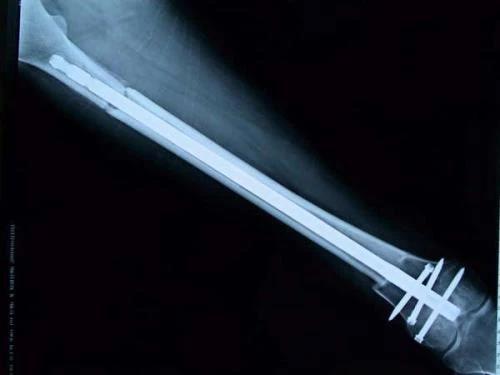

新輔助化療的目的是盡早殺滅遠處微小轉(zhuǎn)移灶,縮小腫瘤及周圍炎性水腫反應區(qū),以利于后續(xù)的保肢手術;觀察腫瘤對化療的敏感性,為進一步指定個體化的術后化療方案奠定基礎。骨肉瘤新輔助化療下的保肢治療如下圖所示: